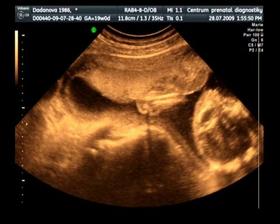

Naše maličké